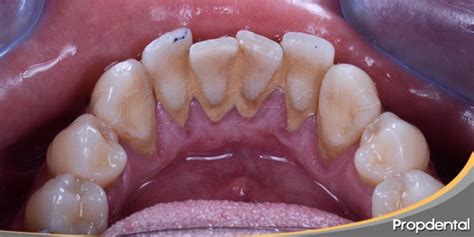

El sarro dental, también conocido como cálculo, es un depósito duro de color amarillento o marrón que se forma en los dientes. Está formado por partículas de comida, bacterias y otros microbios que se quedan atascados en nuestra boca y acaban calcificándose (endureciéndose). El sarro dental puede provocar la acumulación de placa y la enfermedad de las encías si no se trata.

El sarro es un depósito mineral duro en los dientes que puede provocar enfermedades de las encías y caries si no se trata. Se presenta en dos formas:

- Sarro Supragingival: Se forma por encima de la línea de las encías.

- Sarro Subgingival: Reside por debajo de la línea de las encías.

Lo primero es lo primero: mírate en el espejo. Si ves manchas descoloridas en tus dientes delanteros que no parecen desaparecer con el cepillado, puede ser un signo de sarro dental. El sarro dental tiene el aspecto de manchas amarillentas o vetas de color marrón oscuro a lo largo de la línea de las encías o en cualquier zona donde se acumulen partículas de comida.